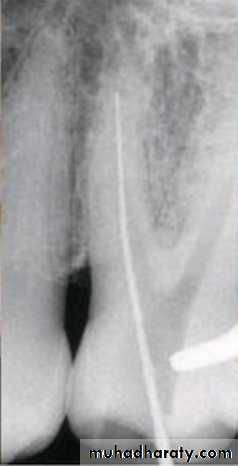

The step-down technique is advocated for cleaning and shaping procedures as it removes coronal interferences and provides coronal taper.

With the pulp chamber filled with irrigant or lubricant, the canal is explored with a small instrument to assess patency and morphology (curvature). The working length can be established at this time.

The coronal one third of the canal is then flared with Gates-Glidden drills or rotary files of greater taper (.06, .08, or .10).

Step-Down Technique

• A large file (such as No. 70) is then placed in the canal, and a watch-winding motion is used until resistance is encountered.

• The process is repeated with sequentially smaller files until the apical portion of the canal is reached. The working length is checked again.

• The apical portion of the canal can now be prepared by enlarging the canal at the corrected working length.